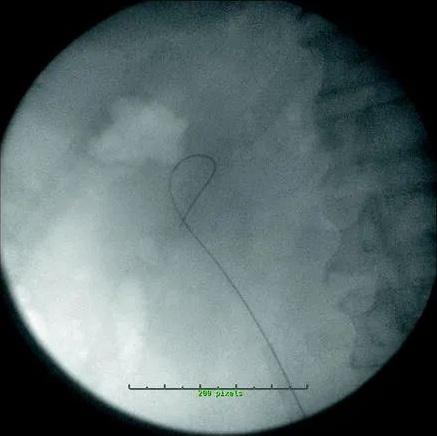

現今, UAS已常用治療腎結石。術前未置入支架的患者,選用12/14 F UAS,術前置入支架的患者,尤其結石負荷較大的患者,選用14/16 F UAS。對於女性,選擇 35 釐米的長度,除非她們的身高低於 152 釐米,在這種情況下,使用 28 釐米的UAS。對於男性,選擇 45 釐米長的 UAS(表 24.2)。用直導管排空膀胱,如果懷疑合併輸尿管結石,則使用 8-10 同軸擴張器擴張遠端輸尿管,並使用低於 7.0 F 的半剛性輸尿管鏡檢查輸尿管。如果懷疑沒有輸尿管結石,則透過 5 F 開口導管進行逆行腎盂造影。逆行腎盂造影可將結石證明為充盈缺損,識別其他病理,重要的是,它將顯示出上輸尿管和 UPJ 的解剖結構,這將指導 UAS 的放置 。使用 Superstiff 鋼導絲可降低 UAS 推進過程中導絲扭結和彎曲的風險。在透過 UAS 以啟用親水性之前,應用水徹底潤溼 UAS塗層。如果可能,將 UAS 推進到 UPJ 的水平,但如果輸尿管在 UPJ 處有明顯的角度,則必須注意不要過度推進 UAS ,因為 UAS 的剛性尖端會傷害輸尿管或腎臟。 UAS 的推進應始終在透視引導下向下(圖 24.2)。一旦到位,內部閉塞器和 Superstiff 金屬絲就應被移除。然後用 2.0 絲線縫合將護套固定到患者的大腿內側。這可以防止 UAS 在手術過程中滑出,從而減少在沒有內部閉孔器就位的情況下,重新定位通路鞘造成的潛在輸尿管損傷。使用加壓沖洗系統,然後用輸尿管軟鏡仔細檢查腎臟。透視可以幫助這個過程,並且所有的腎盞都應該被視覺化。目標視覺化後,鈥激光纖穿過時應注意保證鏡面筆直,以免損壞脆弱的內通道。300 μm 纖芯尺寸的光纖用於最大化透過內窺鏡的流量,而不是限制偏轉,並減少偏轉機構的磨損。6 Hz 頻率下 0.6 J 的鐳射能量設定是典型的啟動設定。如果結石看起來非常緻密,則根據需要選擇更高的能量和脈衝率。結石破碎後,用 1.5 F 無尖鎳鈦諾取石籃去除碎片。必須小心不要試圖取出太大的碎石塊,否則可能會損傷輸尿管。取出碎片後,緩慢撤回 UAS,同時用輸尿管鏡檢查輸尿管。這樣做是為了確保輸尿管中沒有遺漏結石,並且沒有看到輸尿管的其他病理。移除鞘管後,進行另一次逆行腎盂造影,放置 6 F 輸尿管支架,並排空膀胱。